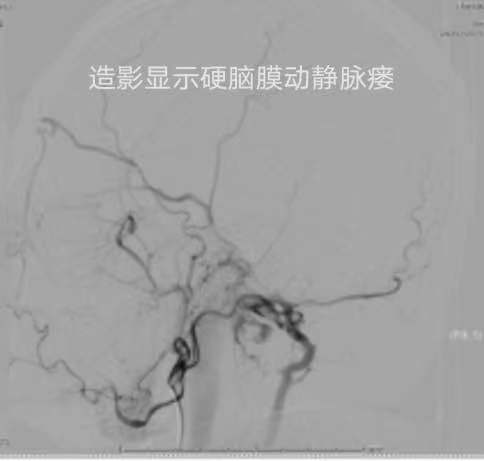

通常情況下腦血管造影術都是經股動脈途逕行主動脈弓及腦血管造影,技術相對成熟。但是股動脈穿刺造影術後壓迫股動脈穿刺點止血時間長,需臥床12-24小時,還容易出現腹股溝皮下血腫、下肢麻木、尿瀦留等不適感。而呂大爺兒女在外,愛人身體欠佳,無法進行術後臥床時段的護理。為解除呂大爺的後顧之憂,首席專家王智教授親自為呂大爺經橈動脈穿刺行腦血管造影術,術中過程順利,明確了臨床診斷為頸靜脈孔區硬腦膜動靜脈瘺,右側頸外咽升動脈腦膜支主供血,可見逆流的眼上靜脈及異常的枕下靜脈及椎靜脈引流,術後穿刺處採用橈動脈壓迫器止血,無需臥床即刻可以下地行走,日常生活自如,無需特殊照顧。呂大爺逢人就是說:市一院王智教授的技術真好,身體沒有任何不適。呂大爺已於當天下午治癒出院。